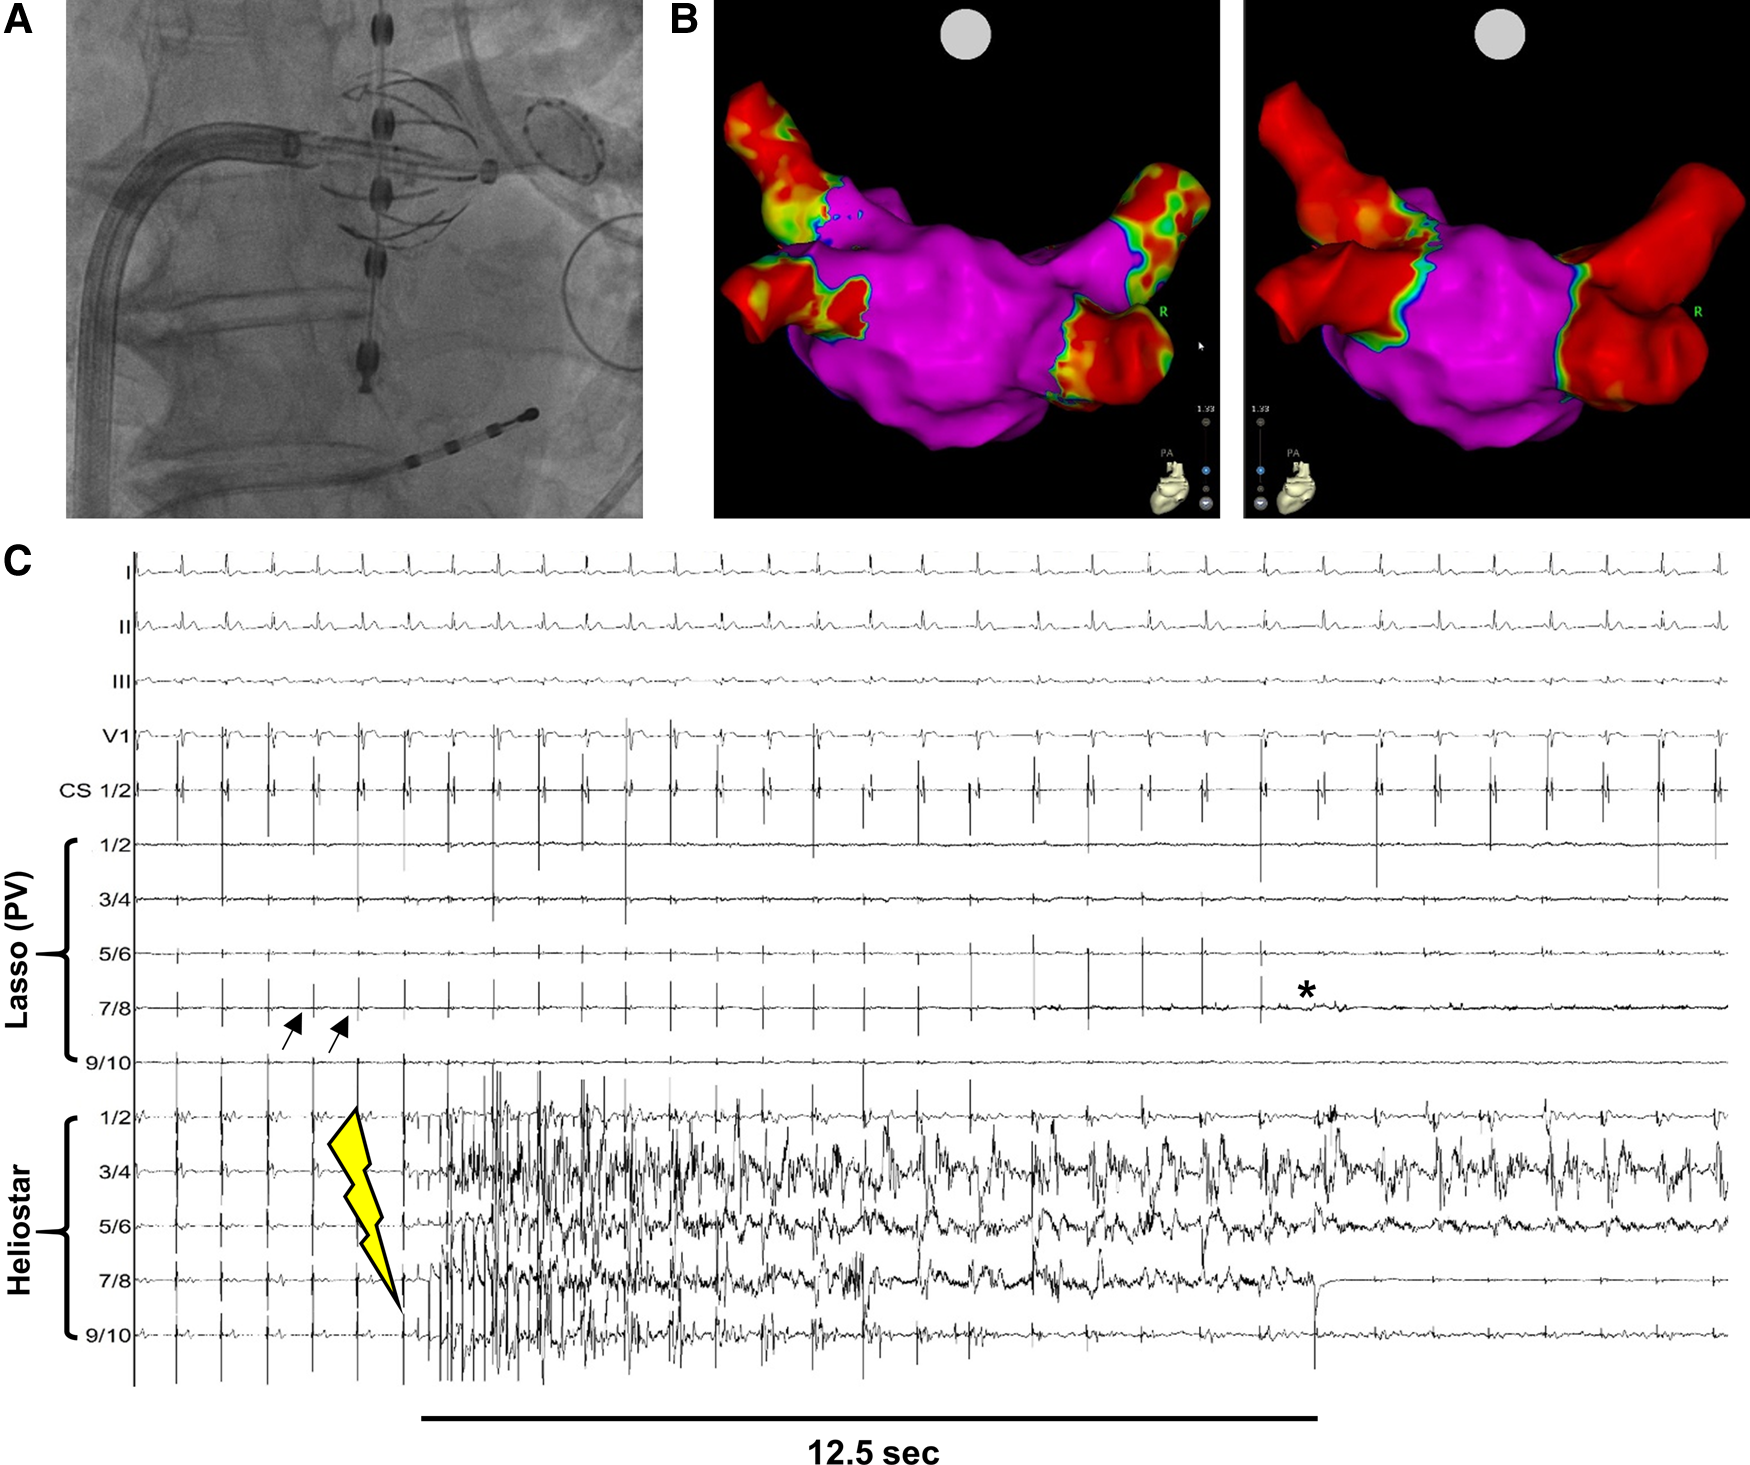

Figure 1

Example of PVI with the novel multielectrode RF-balloon catheter. (A) Fluoroscopy-guided angiography to verify contact between HELIOSTAR™ and left superior PV-ostium. The oesophageal temperature probe is positioned in direct proximity to the ablation catheter. (B) Left atrial electroanatomical, bipolar map before (left) and after (right) PVI by HELIOSTAR™. Note the clearly demarcated ostial lesions after ablation. (C) Example tracing during PVI with HELIOSTAR™. Black arrows indicate PV-signals in the LASSOSTAR™ catheter, with entrance block after PVI (*). Yellow flash-symbol indicates start of ablation. PVI is achieved after 12.5 s. PV, pulmonary vein.

In the first 40 patients treated with the multielectrode RF-balloon catheter at our center, 157/157 pulmonary veins (PVs) could be successfully isolated, including three cases with left common PV-ostia. In 115 PVs (73.2%) ablation was achieved by a “single-shot” RF-application. This includes single-shot PVI in PVs with measurable ectopic PV-activity, as well as PVs with no local activity at the time of ablation but at which procedural target values regarding RF-energy application were met. In PVs in which ectopic PV-activity could be detected via the LASSOSTAR™ or in the balloon electrodes prior to ablation (n = 66) (Figure 1C), median TTI was 11.0 s (Q1 = 8.0 s; Q3 = 13.8 s). Median procedure duration (“skin-to-skin”) was 62.5 min (Q1 = 50.0 min; Q3 = 70.5 min). This also included time to LA-access (median = 11.0 min; Q1 = 8.3 min; Q3:14.0 min) and mapping time (median = 9.0 min; Q1 = 7.0 min; Q3 = 10.0 min). Median LA-dwell time was 28.5 min (Q1 = 23.3 min; Q3 = 36.5 min) and median duration of RF-energy application was 5.0 min (Q1 = 4.0 min; Q3 = 6.8 min). A 3D-remap was performed in six cases (median duration = 8.0 min; Q1 = 6.0 min; Q3 = 10.5 min) (Figure 1B), in the other cases persistent post-procedural PVI was verified by real-time electrogram analysis with the help of the LASSOSTAR™ catheter. Median fluoroscopy duration was 11.6 min (Q1 = 10.1 min; Q3 = 13.7 min) and median fluoroscopy dose amounted to 3.1 Gyxcm2 (Q1 = 2.4 Gyxcm2; Q3 = 4.3 Gyxcm2).